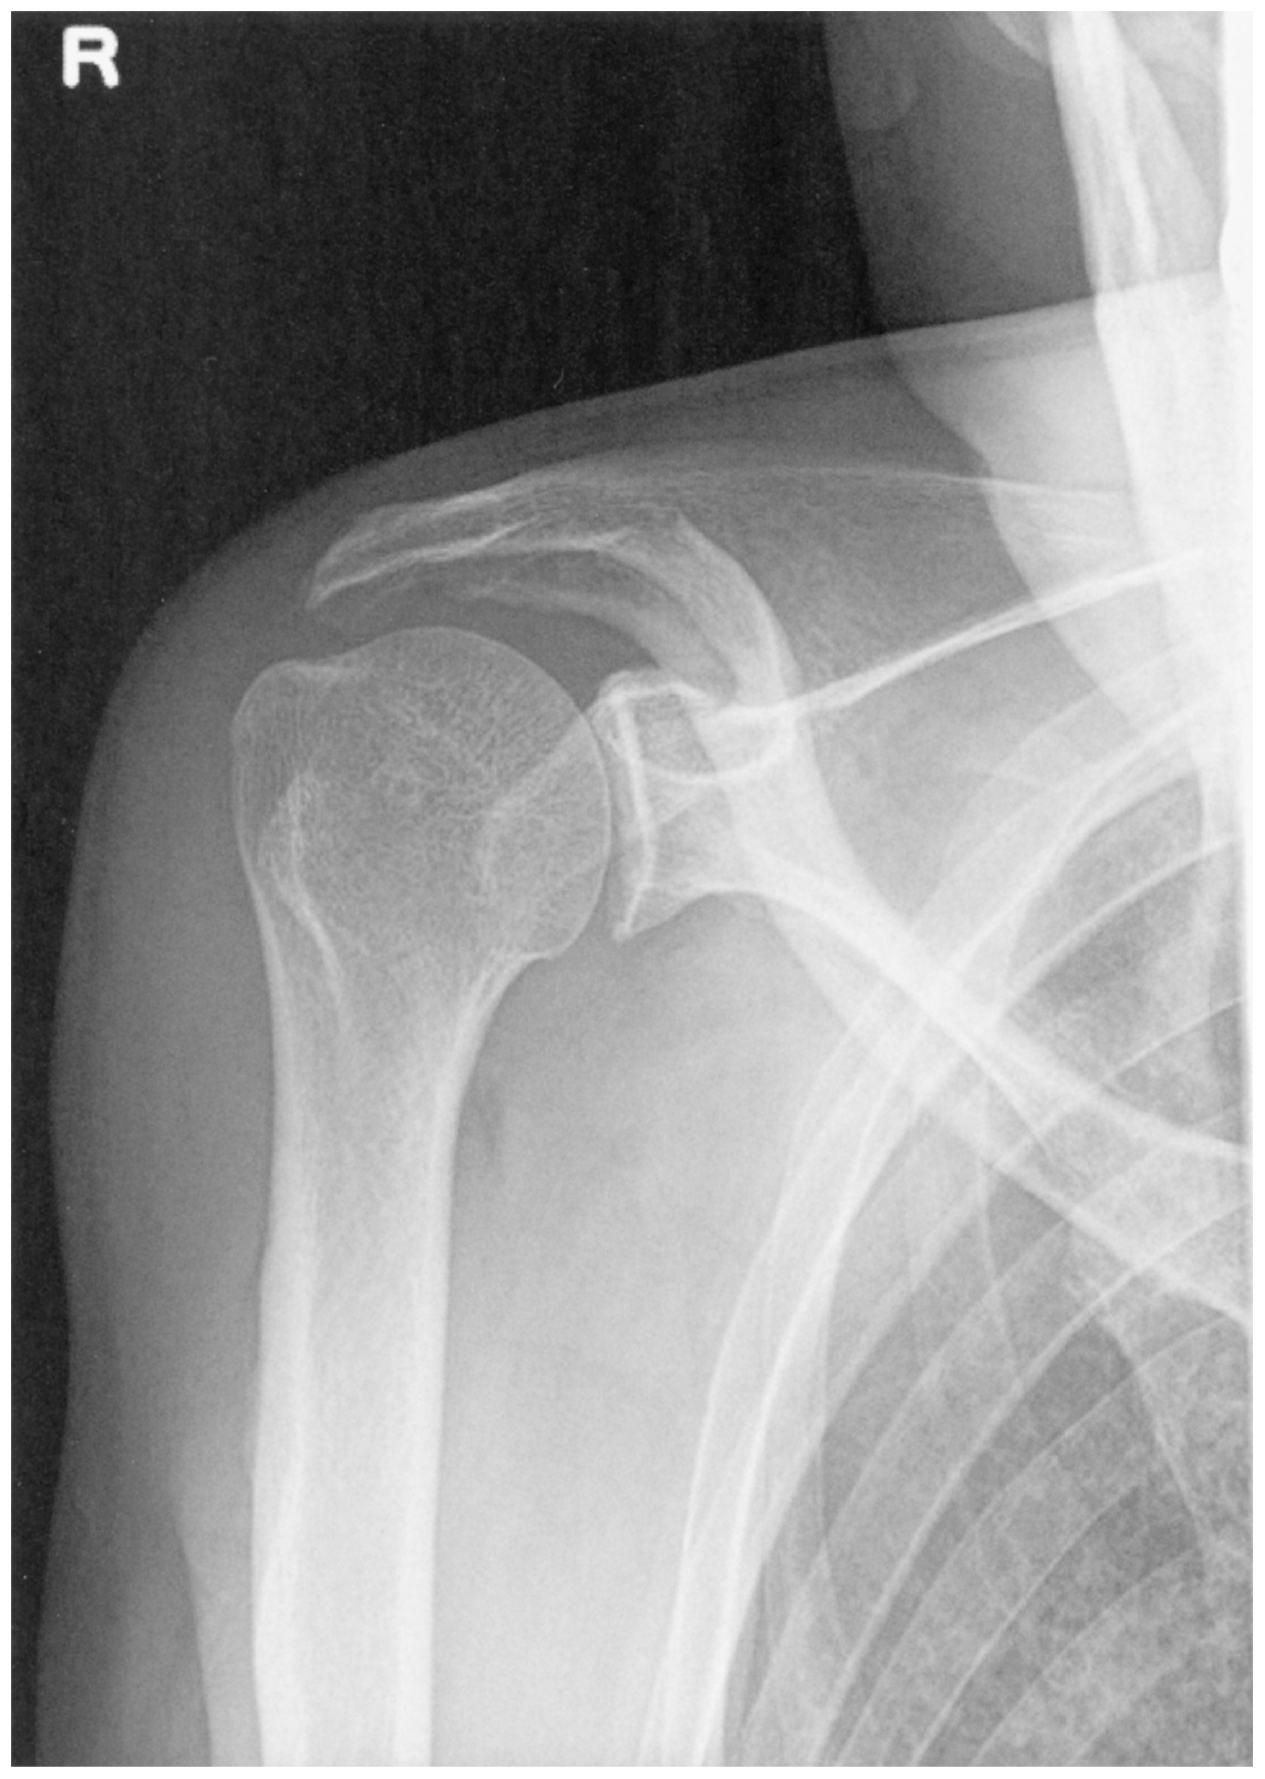

63歳の男性。右上肢の挙上困難を主訴に来院した。4週間前に農作業中に転倒した際,右手をついた。その後右肩の動作時や夜間の疼痛が続くため,市販の鎮痛薬を内服していた。自動的には右上肢の挙上はできないが,右肩関節の他動的な可動域は正常であった。肩関節エックス線写真を下に示す。